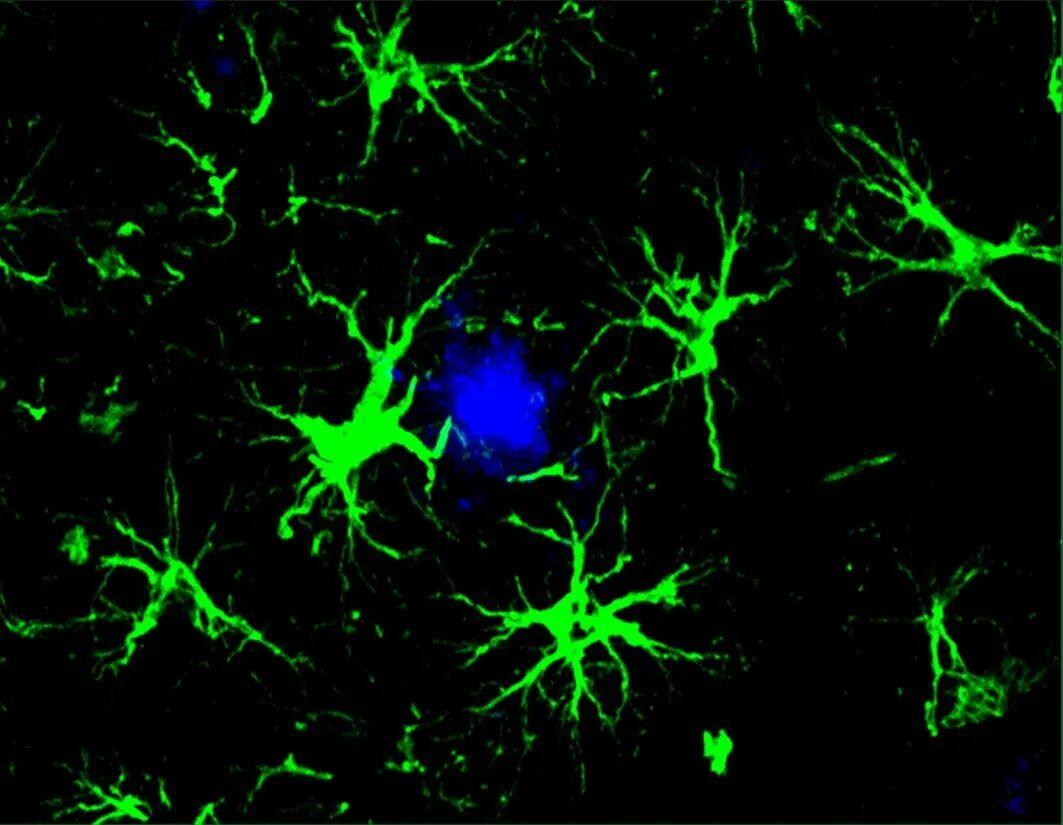

CAR-A疗法(绿色)成功地降低了小鼠大脑中有害的β-淀粉样蛋白斑块(蓝色部分)的数量(来源:Yun Chen,WashU Medicine)

分析结果显示,在第一组更年轻的小鼠中,CAR-A疗法能够阻止β-淀粉样蛋白斑块的形成。在接近6个月大时(此时未经治疗的小鼠的大脑通常已经充满了有害的斑块),接受治疗的小鼠大脑中无斑块形成。与此同时,对于治疗时大脑中已布满斑块的小鼠,接受CAR-A治疗后相较对照组(注射了未携带CAR基因的“空病毒”)β-淀粉样蛋白斑块减少了 50%。